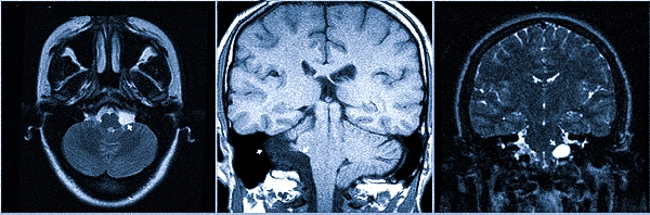

Наиболее распространённые опухоли в этой области – это невриномы (шванномы) и менингиомы. При наличии неврином может наблюдаться фрагмент опухоли во внутреннем слуховом проходе, что легко распознать, особенно на МРТ с использованием контраста.

МРТ головного мозга. Шваннома с компонентом внутри каналца.